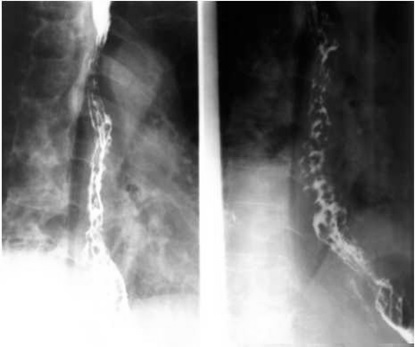

05卷-5.男性,胸骨后隱痛一年,請(qǐng)選擇正確答案(本題滿分2.00分)

本題答案:B

題目解析:【該題針對(duì)“造影-食管靜脈曲張”知識(shí)點(diǎn)進(jìn)行考核】